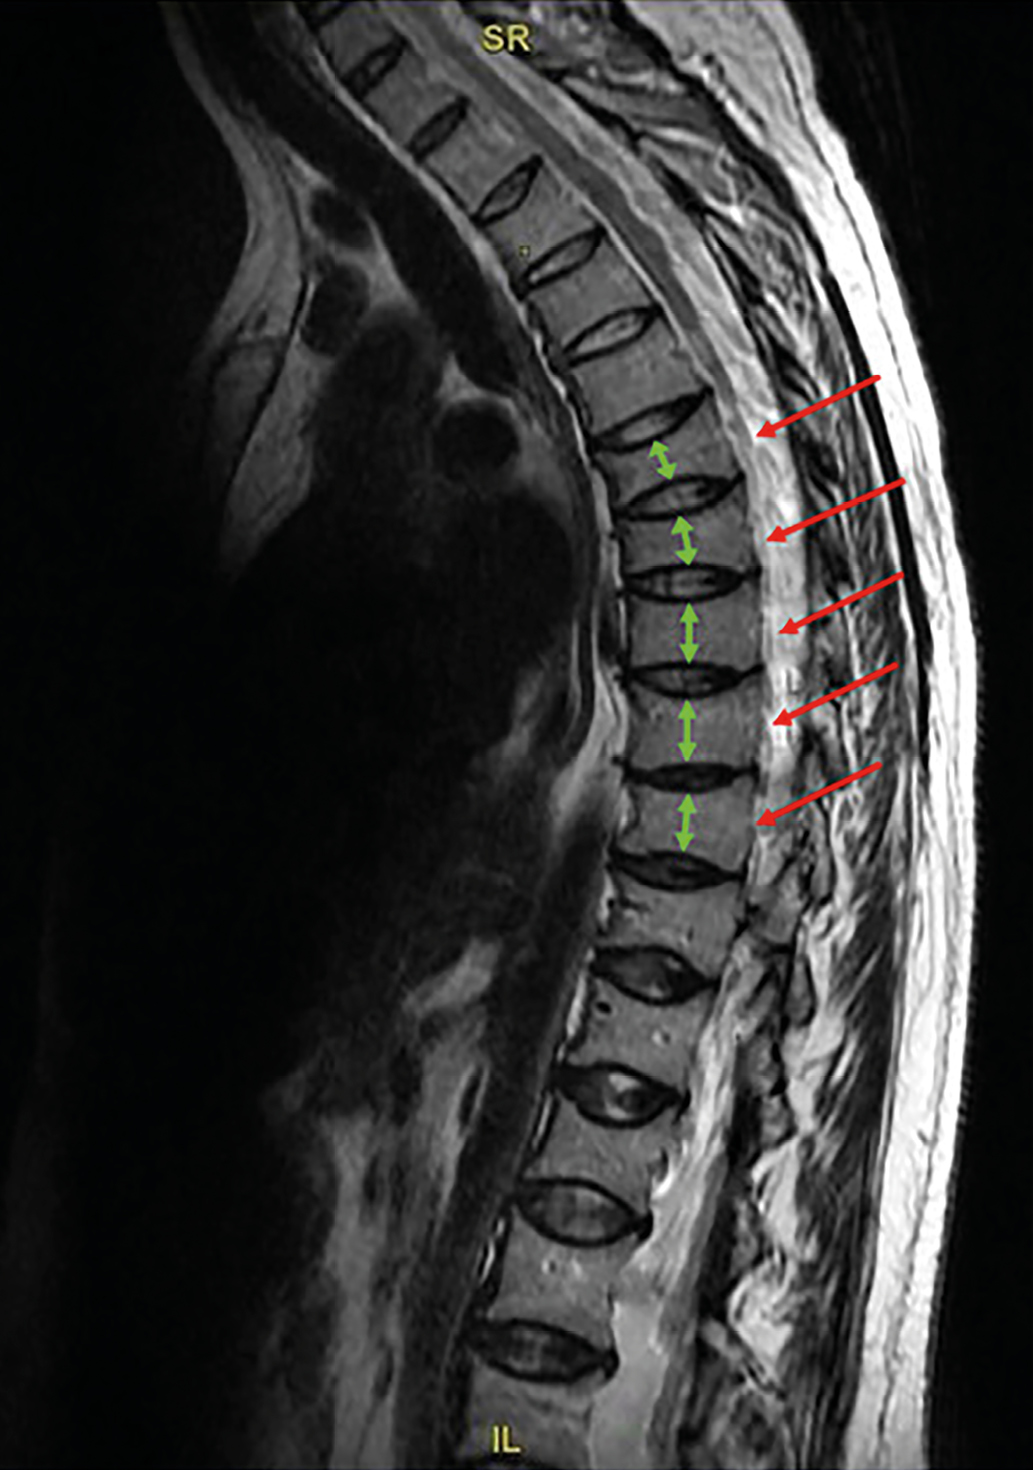

Рисунок 1. Магнитно-резонансная томография грудного отдела позвоночника пациентки Б.

Режим Т2-ВИ. Сагиттальный срез.

Определяется двояковогнутая деформация замыкательных пластин тел Th3-Th12 позвонков с формированием деформации по типу «рыбьих» позвонков. Высота тел позвонков снижена, форма тел позвонков напоминает двояковогнутую линзу. Описанные изменения наиболее выражены на уровне Th4, Th6, Th7, Th10, Th11 позвонков, где степень снижения высоты тел превышает 40% (максимальные значения достигают 46%).

Figure 1. MRI of the thoracic spine of patient B.

T2-WI. Sagittal view.

The following is observed: Biconcave deformation of the endplates in the vertebral bodies of Th3–Th12, resulting in «fish vertebrae» deformities. The vertebral body height is reduced, and their shape resembles a biconcave lens. These changes are most pronounced at the levels of Th4, Th6, Th7, Th10, and Th11, where the degree of vertebral height reduction exceeds 40% (with maximum values reaching 46%).

Основные рентгенологические признаки остеомаляции включают структурные изменения костной ткани, проявляющиеся в генерализованном снижении ее видимой плотности, деформации позвонков и характерных псевдопереломах — зонах Лоозера. Последние представляют собой просветления шириной 2–5 мм, перпендикулярные длинной оси кости или надкостницы и ограниченные склеротическими краями — синдром Милкмана [22]. На МРТ-снимках симметричная двояковогнутость («рыбьи позвонки») формируется вследствие прогиба мягкой позвоночной кости под давлением межпозвоночных дисков. Эти изменения служат ключевым диагностическим признаком остеомаляции и резко контрастируют с переднеклиновидными компрессионными переломами тел позвонков, типичными для остеопороза [23].

DXA не позволяет достоверно оценить степень нарушения минерализации костной ткани, что требует применения дополнительных методов диагностики. Отсутствие компрессионных переломов, характерных для остеопороза, и наличие двояковогнутых деформаций тел позвонков на МРТ («рыбьи позвонки») служат важным диагностическим критерием остеомаляции. Дополнительным фактором, опровергающим диагноз ОБЛ, является продолжающееся у пациентки прогрессирование болевого синдрома, несмотря на прирост МПК на фоне применения антирезорбтивной терапии.